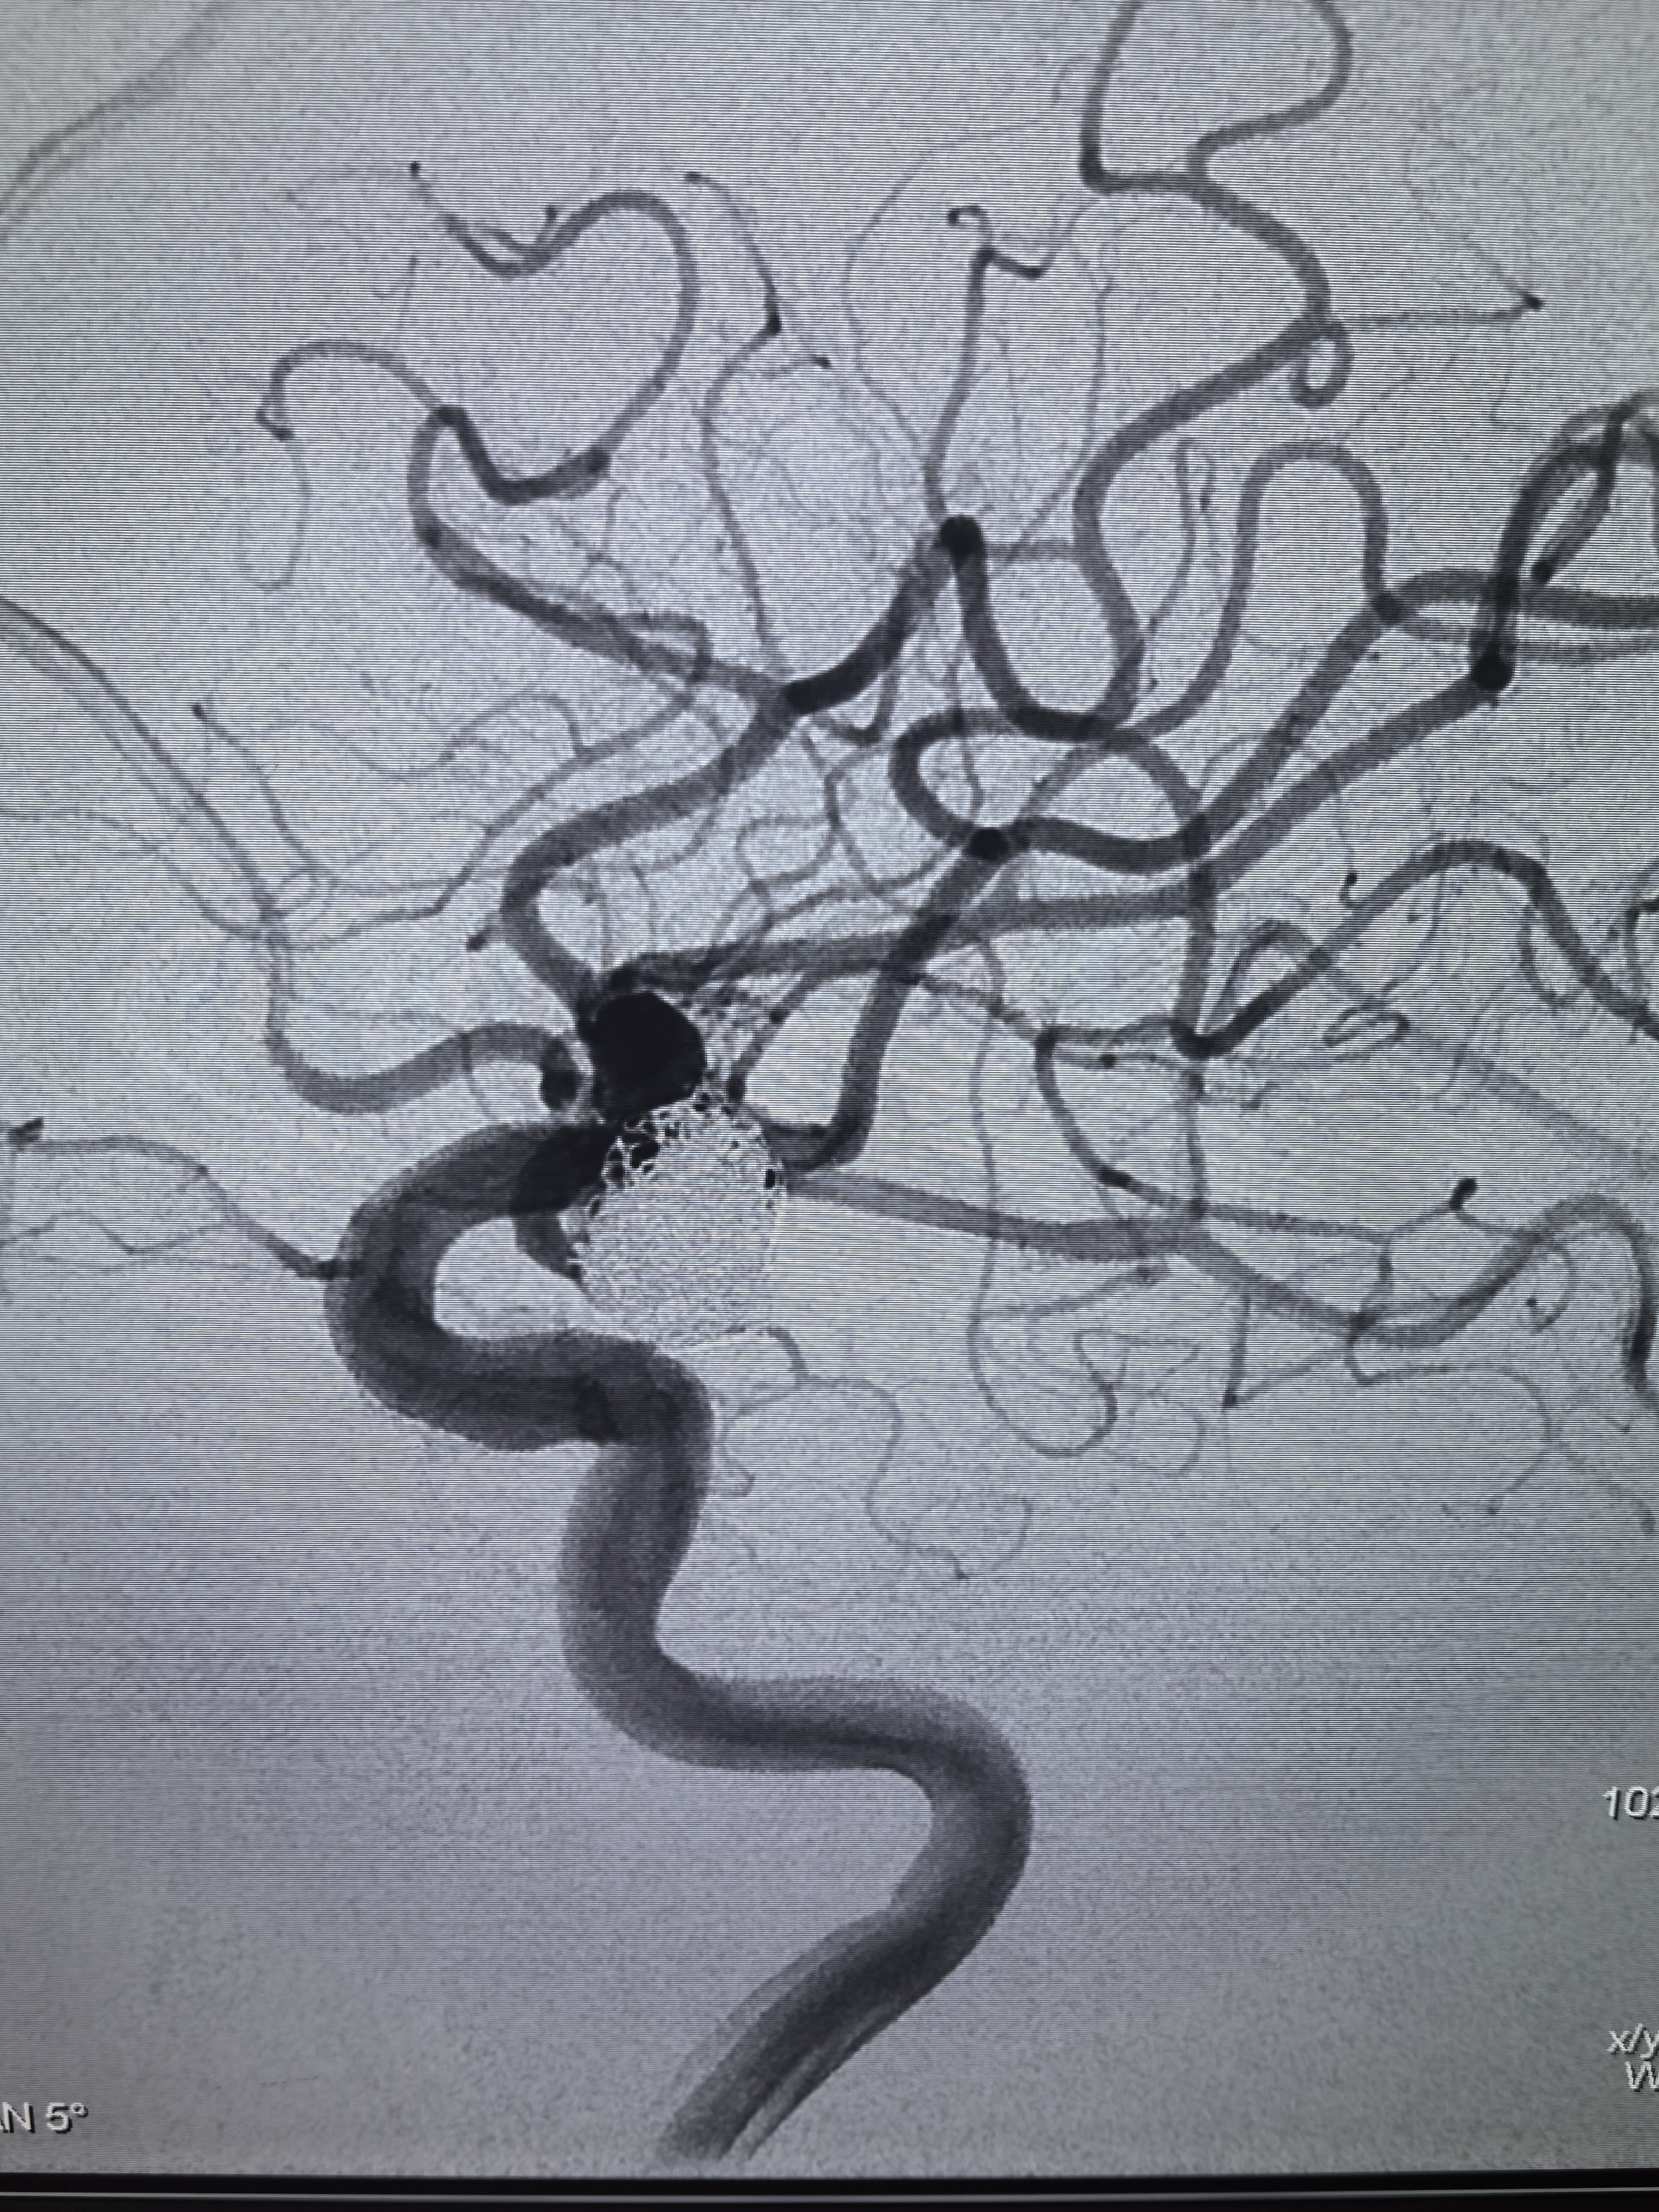

左侧颈内动脉造影!

工作位造影!